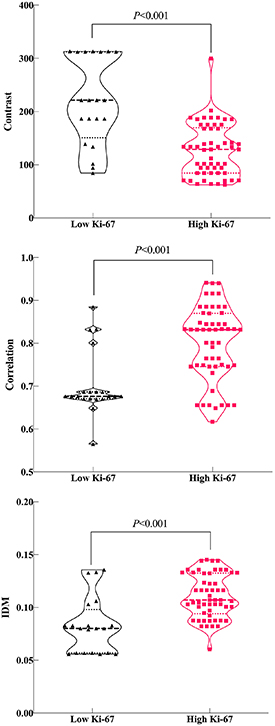

Standard image High-resolution image3.2. Correlations between radiomics features and Ki-67

There were no statistically significant differences in the radiomics features between different CT scanning models(all P-values > 0.1; table 2). In contrast, correlation and IDM were significantly different between the low and high Ki-67 groups (all P-values < 0.001; figures 4(A), (B), and (C). However, there were no significant differences in ASM, SumOfSqs, sum average, sum variance or entropy between the two groups (P > 0.05; table 2). Contrast, correlation, and IDM were entered into the multivariable logistic regression analysis. Finally, contrast (OR = 0.957; 95% CI: 0.926–0.990; P = 0.01) and correlation(OR = 2.5*105; 95% CI: 7.560–8.9*109; P = 0.019) were considered independent risk factors for combined model building with logistic regression (table 3). Combined predictor = contrast-283.340*correlation. In contrast, ASM (r = − 0.285, P = 0.014), contrast (r = − 0.449, P < 0.001), correlation (r = 0.552, P < 0.001), IDM (r = 0.458, P < 0.001), and entropy (r = 0.285, P = 0.014) strongly correlated with the Ki-67 scores (table 4). Overall, higher ASM and contrast were associated with low Ki-67 scores, while correlation, IDM and entropy increased with high Ki-67 scores.

Figure 4. Violin plot of the contrast (A), correlation (B), and inverse difference moment (IDM) (C) features.